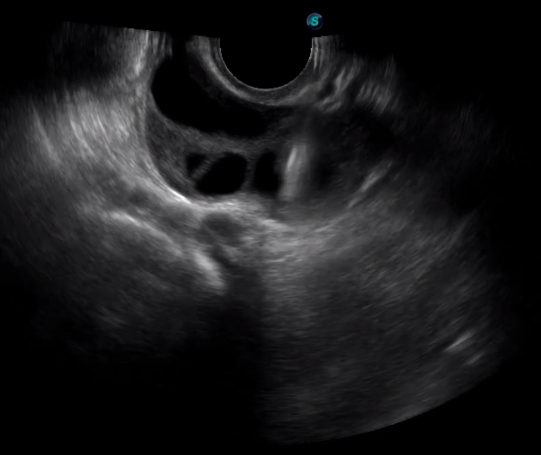

傳統(tǒng)腔內(nèi)探頭采用直柄設(shè)計,在搭配穿刺架使用時,手術(shù)空間小,不易操作;生殖專用的曲柄探頭,探頭柄采用彎曲成角度設(shè)計,可實現(xiàn)監(jiān)視、取卵兩不誤,搭載穿刺架時,可以清晰顯示穿刺針的進針過程、深度和位置,實時監(jiān)視取卵全過程,保障取卵操作精準與安全。

取卵臨床圖